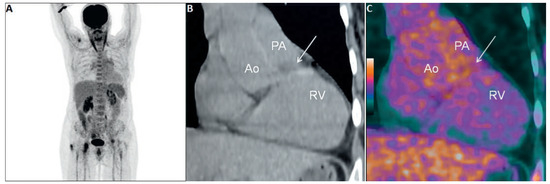

Pulmonary artery sarcomas are uncommon intracardiac tumours with poor prognosis. We report the case of a 69-year-old woman in good health presenting with rapidly progressive dyspnoea and an unfamiliar systolic murmur. Echocardiography revealed pulmonary valve stenosis due to an obstructing mobile mass. Imaging [...] Read more.

Pulmonary artery sarcomas are uncommon intracardiac tumours with poor prognosis. We report the case of a 69-year-old woman in good health presenting with rapidly progressive dyspnoea and an unfamiliar systolic murmur. Echocardiography revealed pulmonary valve stenosis due to an obstructing mobile mass. Imaging studies confirmed the presence of a contrast-enhancing lesion adherent to the valve, extending into the pulmonary trunk and right ventricular outflow tract, and suggestive of malignancy. Endovascular biopsy was attempted with no success. Surgical resection with autologous graft valve replacement and pulmonary artery reconstruction was performed. Postoperative histological examination confirmed the diagnosis of an undifferentiated pleomorphic sarcoma. Pulmonary artery sarcoma should be considered as a rare differential diagnosis in patients presenting with dyspnoea and a crescendo–decrescendo systolic murmur increasing with inspiration. Echocardiography is a useful first diagnostic approach but multi-imaging assessment is almost always necessary for definite diagnosis. Our case provides insights into the challenges met by cardiologists, radiologists and cardiac surgeons in the management of such cases. Full article

Show Figures

Figure 1